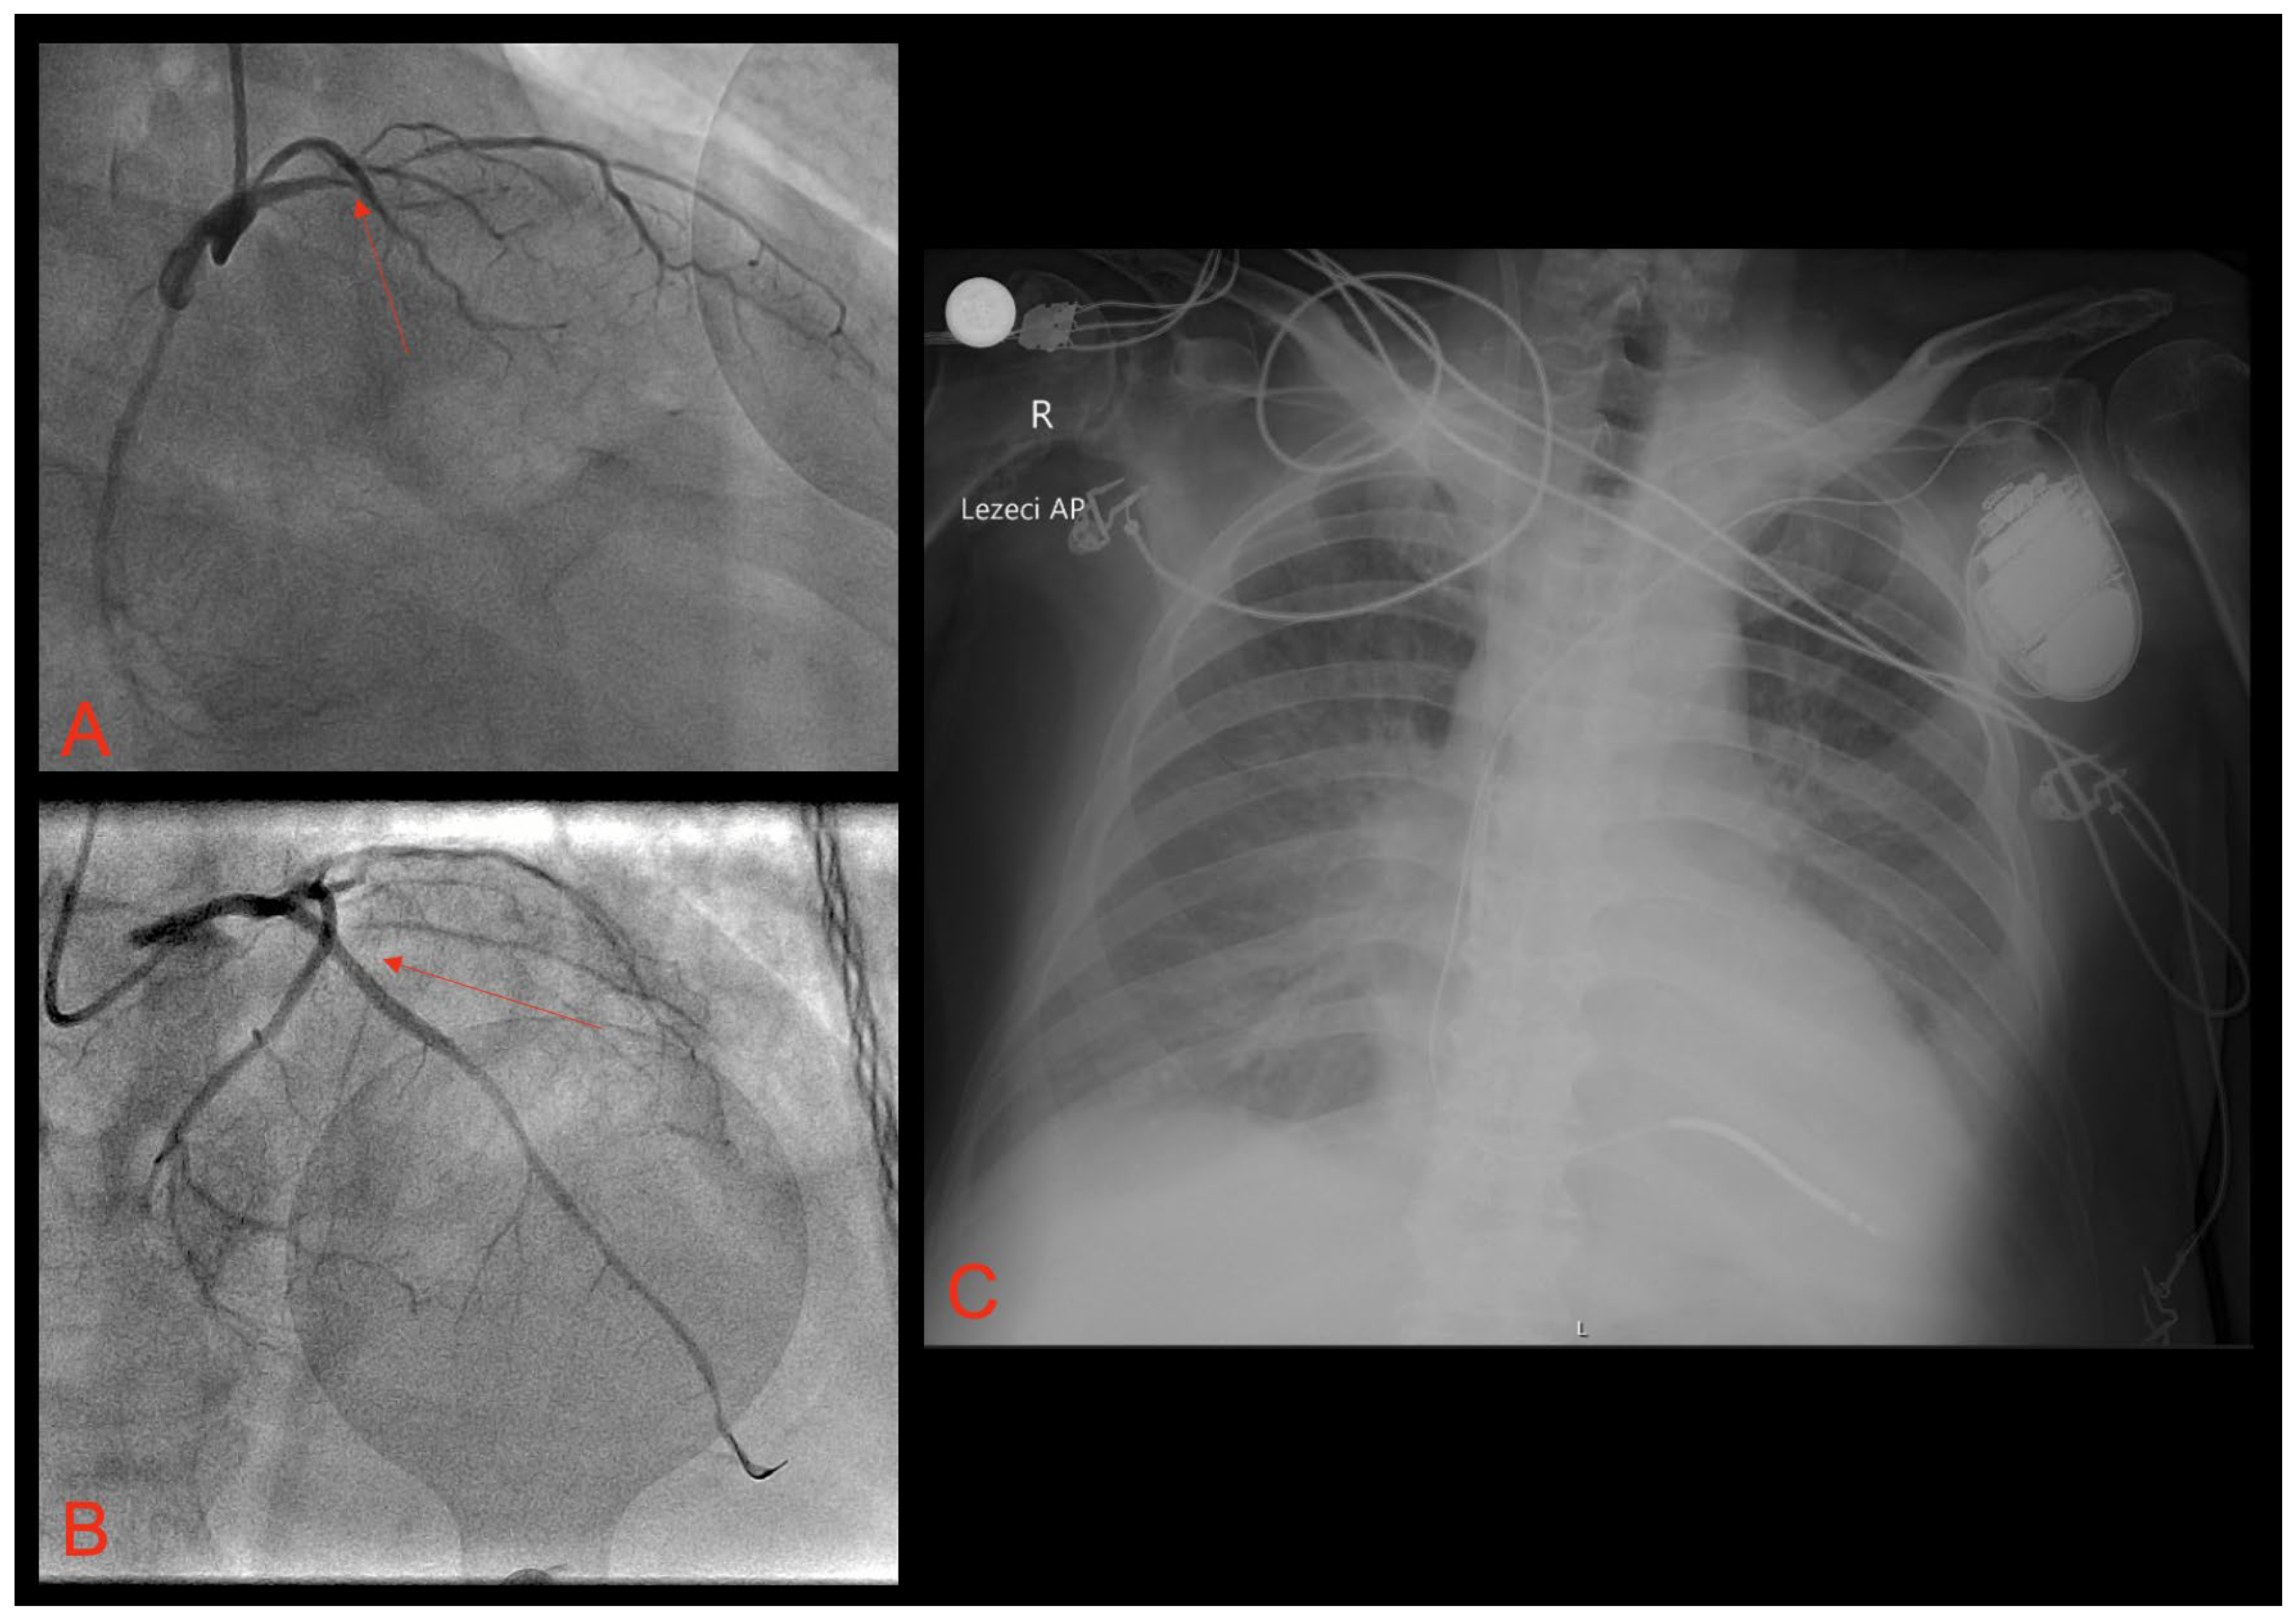

2. Case Report